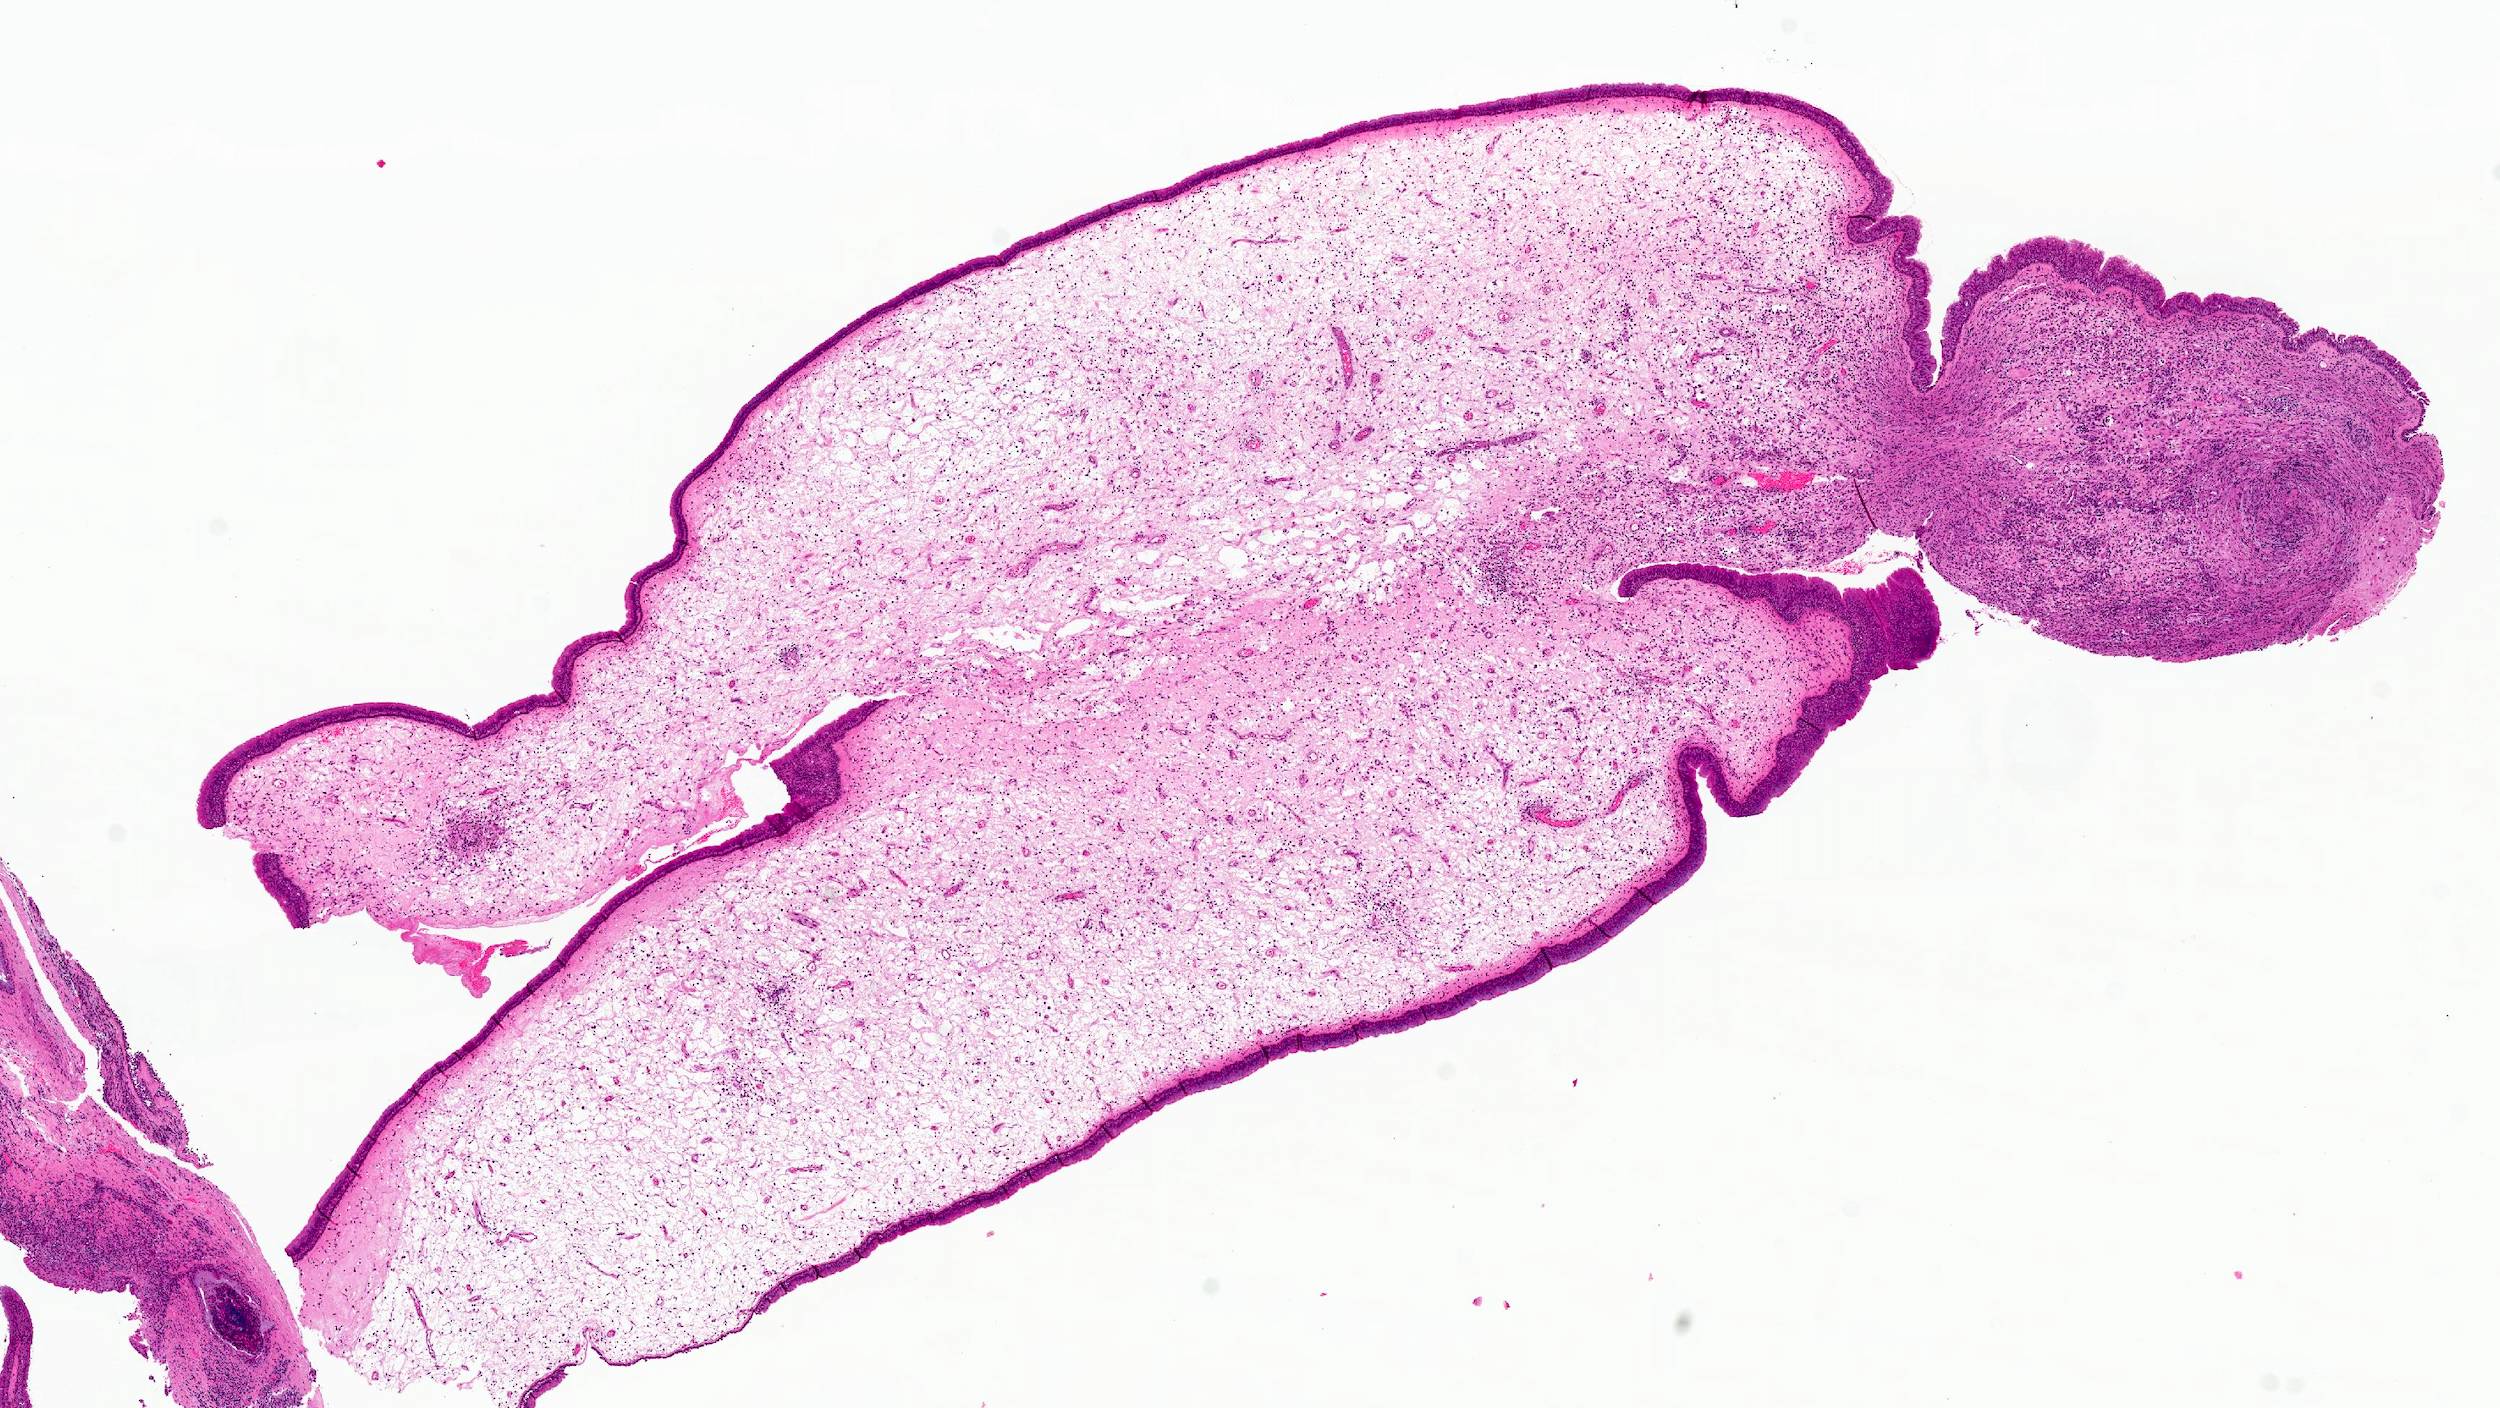

Microscopic (histologic) description

- Edematous, fibrotic or loosely myxoid stroma covered by respiratory epithelium

- Infiltrated by mixed inflammatory cells, including lymphocytes, plasma cells, eosinophils, neutrophils and mast cells

- Surface epithelium can show ulceration or squamous metaplasia

- May have bizarre stromal cells (large and pleomorphic)

- Submucosal glands are decreased or absent

- Concurrent fungal infection may be seen

- Rarely, osseous metaplasia may be present

Microscopic (histologic) images